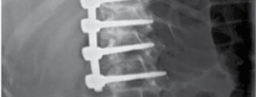

Clinical & Radiographic Imaging Archive